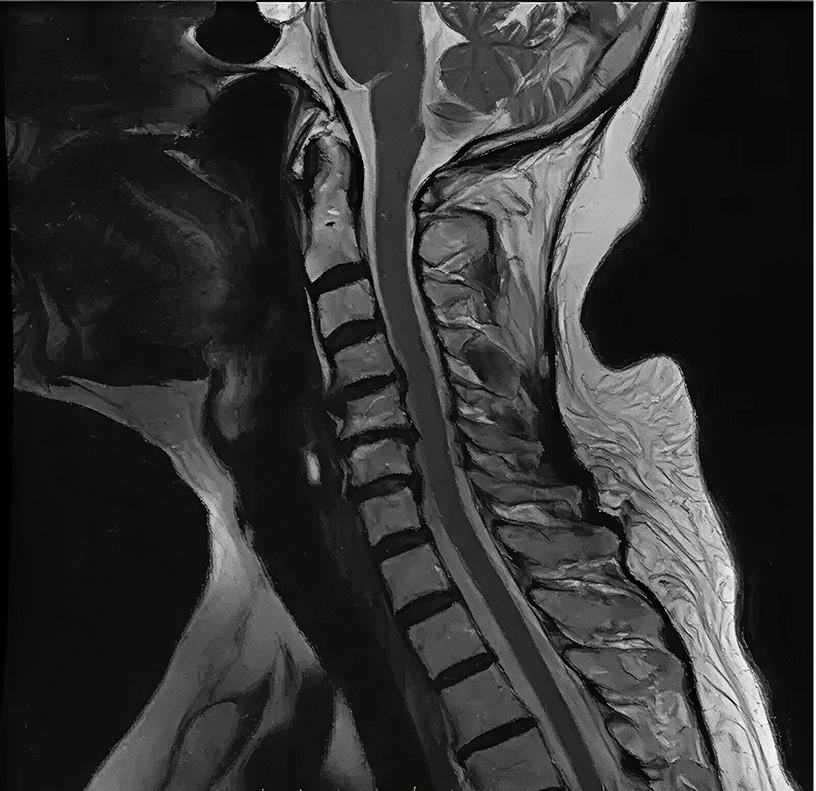

Columna cervical

En nuestra unidad de columna cervical, brindamos atención integral, profesional y humana al paciente con patologías de la columna vertebral, a cargo del equipo liderado por el Dr. Diego Méndez Rosito y su grupo de neurocirugía de columna. Abordamos desde el diagnóstico hasta el tratamiento quirúrgico y de mínima invasión, siempre con la experiencia en neurocirugía avanzada, microcirugía e instrumentación vertebral que nos distingue.

La columna cervical corresponde a las primeras vértebras de la espalda (generalmente entre C1-C7) que estabilizan y dan movilidad al cuello, mientras protegen la médula espinal y las raíces nerviosas que salen hacia los brazos. Cuando aparecen lesiones o degeneración en esta región, pueden producirse dolores de cuello, irradiación a los brazos, debilidad, hormigueo, alteraciones de equilibrio o incluso daño de la médula espinal.

- Diagnóstico de vanguardia: empleamos imagen de alta resolución (resonancia magnética, tomografía), estudios neurofisiológicos y análisis clínico multidisciplinario para establecer el plan óptimo.